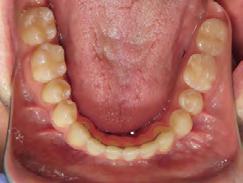

4). Archwires were upgraded incrementally into 19 x 25 SS. Once the bite was completely closed, the patient was referred to the myofunctional therapist to begin treatment. Eight sessions of myofunctional exercises were performed, focusing on muscle building, toning, synchronicity and awareness. Improvement in correct chewing, swallowing and resting postures of the lip and tongue were addressed. All appliances were removed 21 months after initial insertion (Figure 5), and the patient was referred to a re-

storative dentist for veneers on the maxillary central incisors; the patient opted for gold veneers (Figure 6). Clear removable retainers were inserted with a fixed mandibular retainer canine-to-canine.

Treatment Results

The patient finished with Class I occlusion, ideal overbite and overjet. The arches are co-

Figure 5. Final records.

ordinated, lateral open bite closed and occlusal cants leveled. From the frontal cephalometric tracings, maxillary width increased from 58 mm to 69 mm. From the lateral cephalometric tracing, the incisor angulations remained unchanged. The final report from the myofunctional therapist indicated the patient eliminated the bilateral posterior tongue-thrust swallowing pattern with saliva, liquid and solid swallows. Correct swallowing mechanics were demonstrated while sipping/gulping liquids from a cup. His day and nighttime tongue-resting postures were reported to be on his incisive papilla, with lateral margins lightly suctioned into the upper arch. Lips were closed and competent diurnally and nocturnally.

Most recent records are two years after removal of the orthodontic appliances, demonstrating the stability of the results (Figure 7).